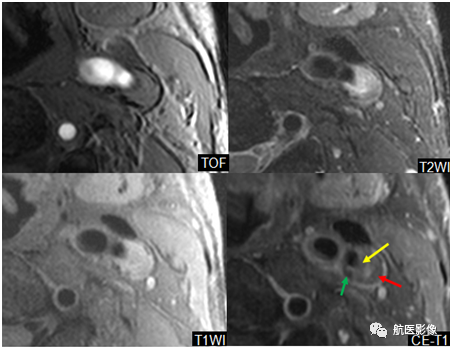

3、4D-CTA技术评估脑动脉瘤破裂风险:

利用心电门控结合4D-CTA成像技术监测动脉瘤壁上的异常搏动点(如球囊吹胀前的局部薄弱点)。 如果在一个心动周期内发现动脉瘤壁上存在异常搏动点,动脉瘤破裂的风险就会显着增加。

上图所示为一名动脉瘤破裂出血的患者。 红色箭头表示动脉瘤壁的异常搏动点(即破裂口)。

4. MRI高分辨率血管壁成像:

可以识别颈动脉不稳定斑块的特征(如纤维帽薄、脂核大、斑块内出血、溃疡、炎症等)并指导临床治疗。

左侧颈内动脉起始部形成斑块医学影像学简历,有大的脂质核心(红色箭头)和少量钙化(绿色箭头)。 表面纤维帽不完整(黄色箭头),被认为是易损斑块。